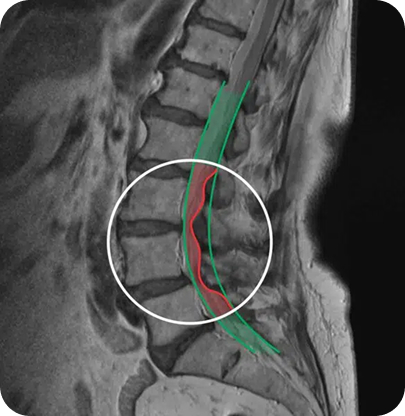

SLIKA MAGNETNE RESONANCE (MRI) - STENOZA

Hrbtenični kanal bi moral biti čez celotno površino enako širok. Rdeče je označena zožitev - stenoza.